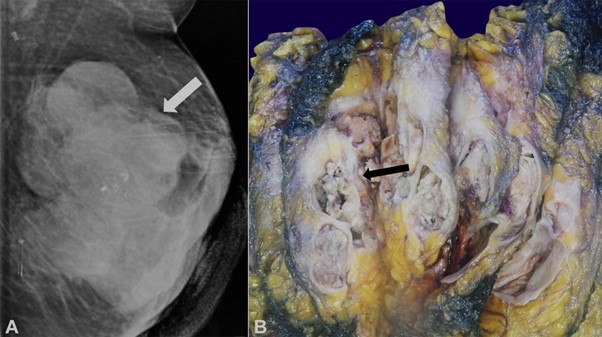

A 49-year-old female presented with the complaint of painful swelling in the right breast for six months. The swelling developed gradually and was associated with nipple discharge. On examination, an ill-defined mass was palpated in the upper outer quadrant of the right breast. The skin surface was blanched and erythematous. The contralateral breast was normal, no axillary lymph nodes were detected on palpation. Ultrasonography (USG) revealed a large heterogeneous, hypoechoic collection with interval septation and lobulation, as well as peripheral vascularity, involving all quadrants of breast and retroaleolar region along with overlying skin thickening, as well as subcutaneous edema. Contralateral breast tissue was found to have normal fibrous glandular tissue. An impression of breast abscess was given. Mammography revealed an ill-defined mass with irregular contours and eccentric lucent areas, as well as soft tissue swelling in the upper and central subareolar regions around the nipple (Figure 1A). The left breast appeared to be normal. No evidence of lymph node involvement was reported. Fine needle aspiration cytology (FNAC) was performed from the right breast mass, revealing inflammatory cells, cystic macrophages, and degenerated cells in a proteinaceous background. A trucut biopsy performed from the breast mass showed dense abundant eosinophilic, acellular proteinaceous material, foamy macrophages along with few degenerated cells. Repeat trucut biopsy revealed a few dyscohesive clusters of atypical cells along with similar proteinaceous material, raising suspicion of malignancy.

A simple mastectomy was performed, which on gross examination revealed a grey-white tumor measuring 6.5×4×4 cm occupying the right upper and lower quadrants as well as the retroaereolar region (Figure 1B).